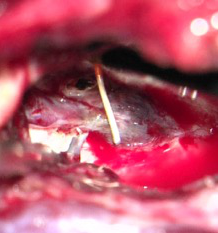

3.开颅手术切除畸形血管团

考虑到患者术前癫痫,且介入术中患者拔管困难,予以行开颅手术切除畸形血管团,并拔出微导管。术中可见微导管及注射的Onyx胶(血管内黄色部分及黑色部分),游离血管后近端用临时阻断夹阻断,远端剪断,打开临时阻断夹将微导管自股动脉鞘拔出,然后切除畸形团。术后复查头颅CT提示钙化及介入术中胶均已切除。